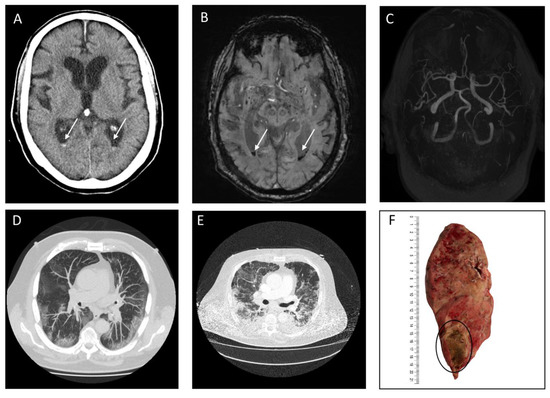

3.2. Imaging and Clinical Findings

| Subarachnoid Hemorrhage (n = 11) | |

| Primary SAH, n (%) | 9 (81.8) |

| • Aneurysmal, n (%) | - |

| • Cortical, n (%) | 9 (81.8) |

| • Bilateral, n (%) | 4 (36.4) |

| • Ventricular extension, n (%) | - |

| Secondary SAH, n (%) | 2 (18.2) |

| Mild lung infection, n (%) | 1 (5.6) |

| Regular lung infection, n (%) | 1 (5.6) |

| Severe lung infection, n (%) | 1 (5.6) |

| Critical lung infection, n (%) | 15 (83.3) |